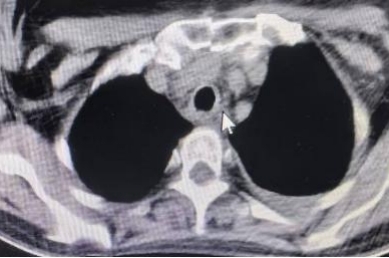

术后

原发性气管肿瘤是指原发于第一气管环以下至隆突以上范围内的气管肿瘤、多起源于气管后壁的膜部与软骨交界处的黏膜上皮和腺体,为呼吸系统的少见病症。成人主气管平均长度12cm,一般手术切除一期吻合最大长度不超过5cm。该患者主气管长度仅10cm,术中切除气管长度4cm,上、下切缘各2mm,切除总长度达4.4cm,近主气管一半长度,术中配合双侧肺门松解最大限度保证气管切除长度、最大限度降低气管吻合口张力,术后未进行下颌前胸减张缝合,大大提高患者术后舒适感加速患者康复。